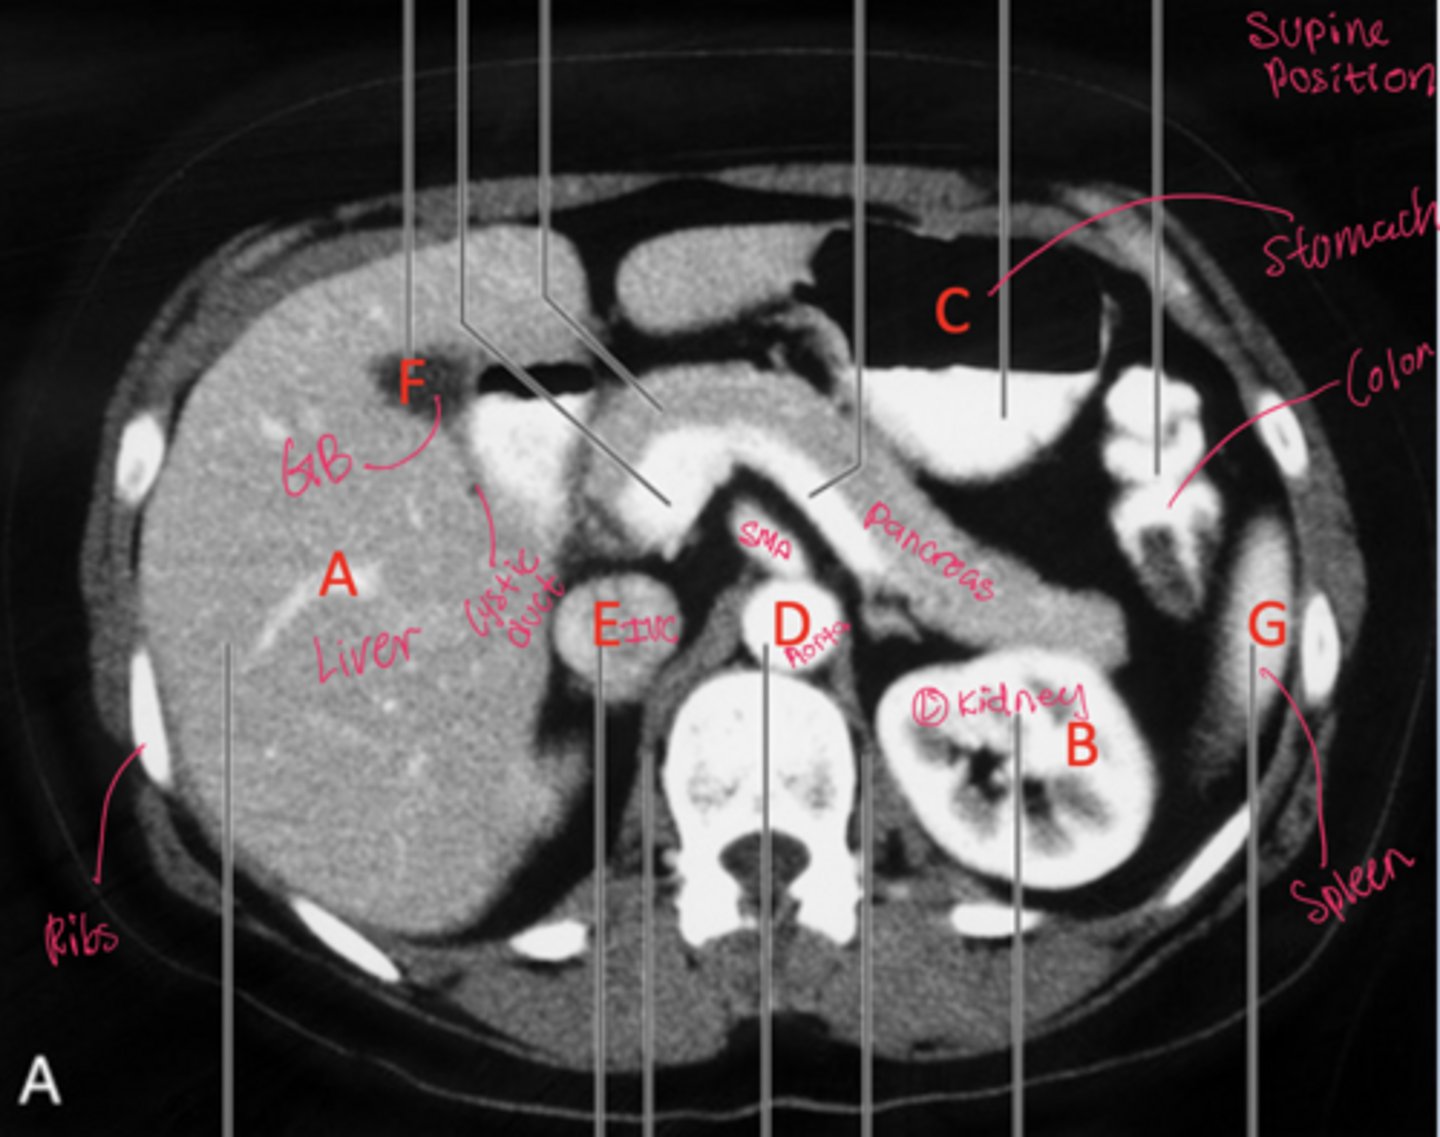

Be able to label the radiograph

How can patient position on CT be determined using fluid and air distribution?

Fluid moves to the dependent (lowest) side, while air rises to the non-dependent (highest) side due to gravity

Where do fluid and air collect on CT when a patient is supine?

Fluid collects posteriorly (toward the back) and air collects anteriorly.